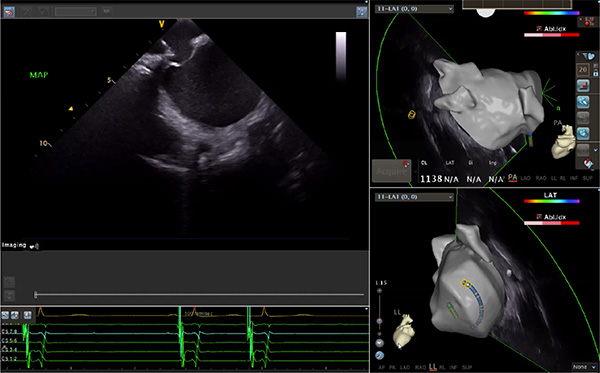

超聲心動圖技術包括常規(guī)經(jīng)胸超聲(TTE)、經(jīng)食管超聲(TEE)、心腔內(nèi)超聲(ICE)、超聲聲學造影(MCE)、三維超聲心動圖等,ICE是一種新興技術——將微型的換能器安裝在心導管的尖端,經(jīng)由外周血管輸送至心腔內(nèi)部,換能器發(fā)射聲波,對心臟及其鄰近組織進行實時高質(zhì)量成像和(或)血流動力學測定的超聲成像技術。基于不同的技術原理,心腔內(nèi)超聲導管被分為兩類:機械旋轉(zhuǎn)式超聲導管和相控陣超聲導管。目前,臨床上主要應用的是相控陣超聲導管,ICE成像通過術者旋轉(zhuǎn)導管及操縱導管手柄上的兩個旋鈕來完成。

ICE門檻高、集成了超聲和圖像處理最前端的技術,是當前內(nèi)窺超聲方向最挑戰(zhàn)的領域。不同于傳統(tǒng)接觸式三維重建方法會產(chǎn)生假腔,影響術者對靶點或結構的判斷,心腔內(nèi)超聲(ICE)可直接顯示心臟結構,有助于理解心臟內(nèi)各部位之間的解剖關系,不僅具有實時成像、并發(fā)癥監(jiān)測以及良好的耐受性,同時以股靜脈入路,無需全麻或深度鎮(zhèn)靜,日益成為心臟介入手術中重要輔助工具,被譽為心臟介入醫(yī)生的“黃金眼”。心腔內(nèi)超聲可用于多種心臟介入手術,潛在患者群體龐大,動脈網(wǎng)測算我國心腔內(nèi)超聲導管市場空間或?qū)⒊?00億元,具有廣闊前景。

隨著心腔內(nèi)超聲的應用更廣,性能也在逐漸優(yōu)化,已從二維成像轉(zhuǎn)變?yōu)?strong>三維成像,極大增強了引導及可視化能力。二維心腔內(nèi)超聲支持雙平面或三平面成像,可顯示兩個或三個不同的平面視圖,但醫(yī)生需將這些圖像在腦海中重新構建為三維解剖結構。三維心腔內(nèi)超聲則可直接呈現(xiàn)三維解剖結構圖,便于醫(yī)生更輕松地開展手術。按照產(chǎn)品發(fā)展方向,預計心腔內(nèi)超聲還將向更清晰、精準、多功能等方向發(fā)展。